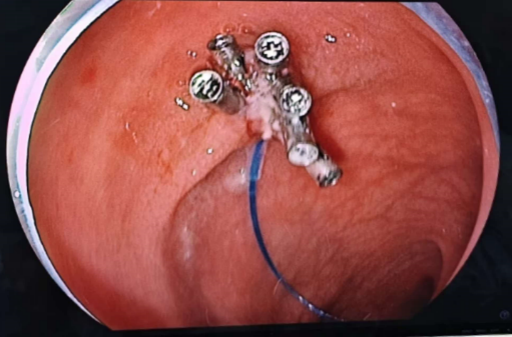

在儿童医学中心、消化内科及麻醉科的多学科协作下,消化内科党支部书记兼内镜中心副主任滕贵根在内镜护士王依晗、孙学信的默契配合下为患儿行巨大息肉切除术,鉴于该息肉体积巨大(占据肠腔约3/4),采用"尼龙圈结扎+止血夹封闭"的双保险手术方案,手术顺利完成,术后创面愈合良好,未再出现便血等不适。

图3 内镜下息肉切除后封闭创面